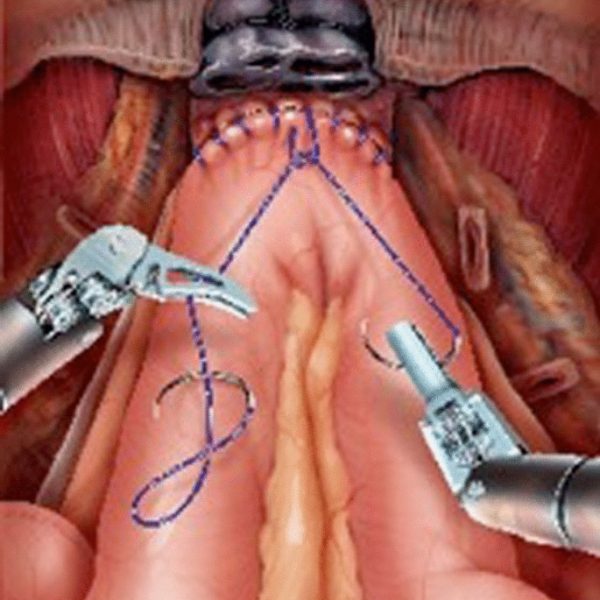

Ameliyat, robotik cerrahi sistemi kullanılarak gerçekleştirilir. Hasta genel anestezi altına alınır ve karın bölgesine birkaç küçük kesi açılır. Robotik kollar bu kesilerden içeri yerleştirilerek cerrah tarafından kontrol edilir. İlk olarak, mesane ve çevresindeki lenf nodları çıkarılır. Erkek hastalarda prostat ve meni keseleri, kadın hastalarda ise rahim, yumurtalıklar ve vajinanın bir kısmı da çıkarılabilir. Sonrasında idrarın vücut dışına atılması için yeni bir idrar yolu oluşturulur.